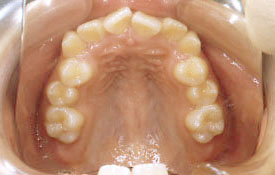

実際に山手矯正歯科クリニックにて、治療された方の例です。

インビザラインの治療例:CASE-1

| プロフィール | 42歳 女性 |

|---|---|

| 所見 | 他院で行われた矯正歯科治療後の後戻りに悩まれて来院されました。 アイライナーの装着は、1日平均20時間ほどでした。 |